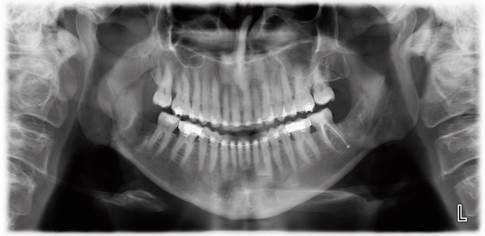

Tras 12 meses de seguimiento, se logra observar una extrusión suficiente para realizar desinclusión del tercer molar con un bajo riesgo de daño al NAI, procedimiento el cual es llevado a cabo sin complicaciones (figura 6).